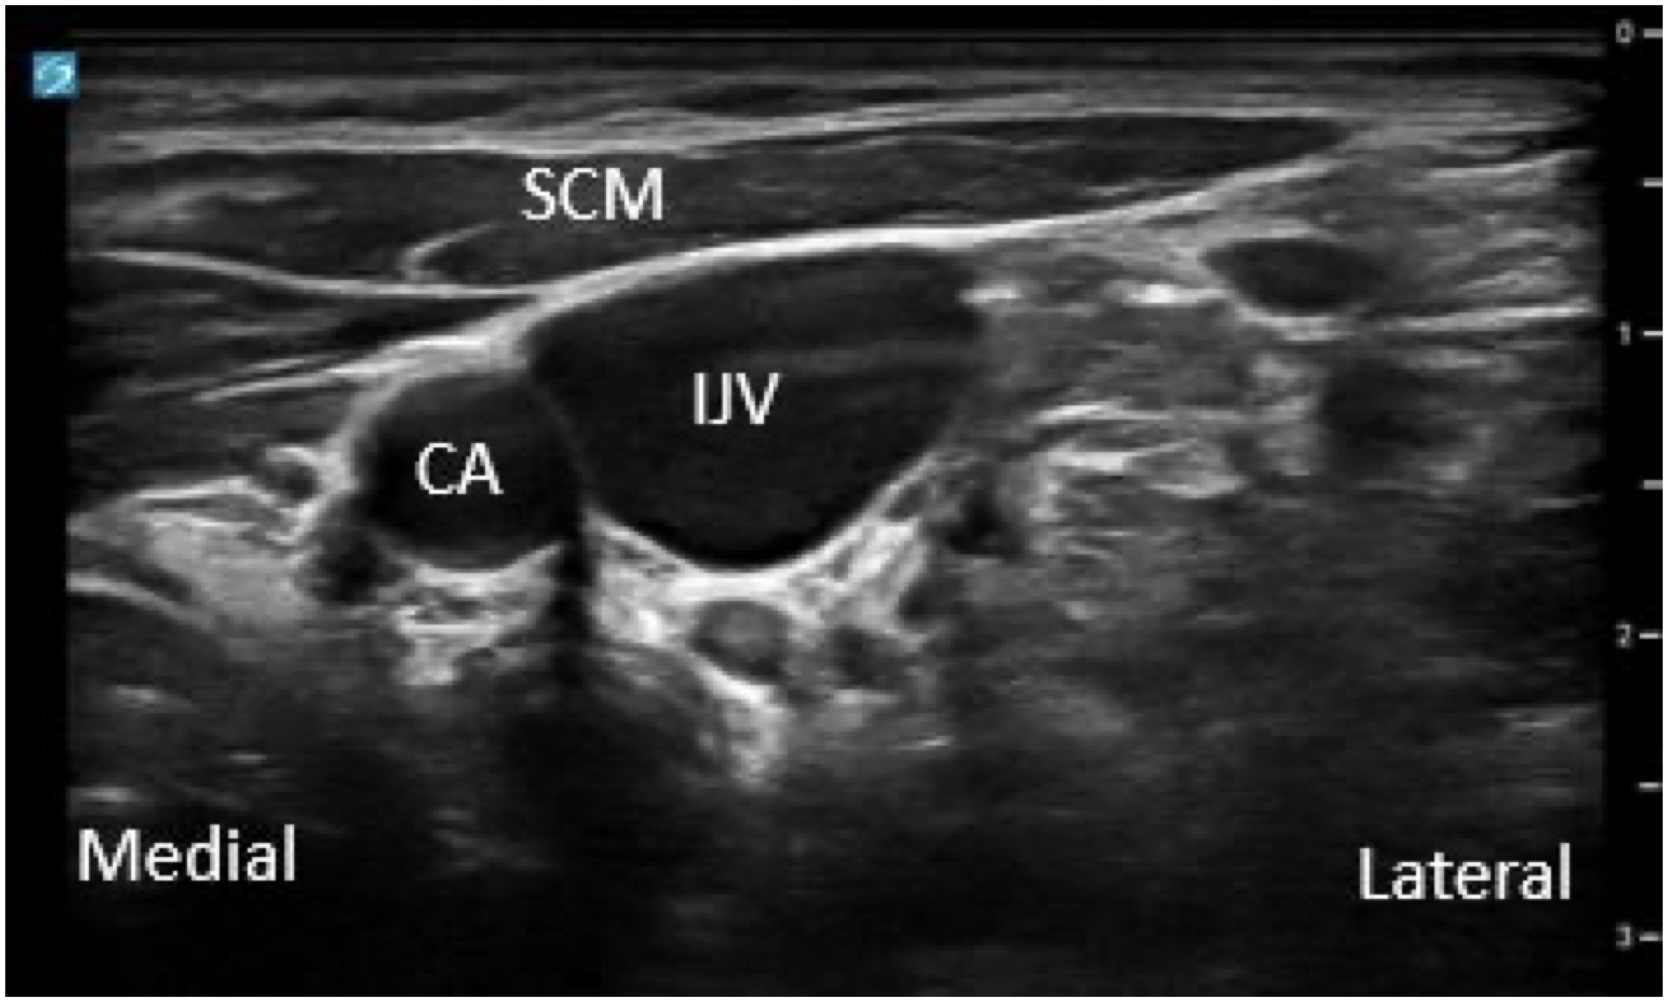

Although ultrasound guidance can assist with central access for various locations, the most common central vein used is the internal jugular vein (IJV). The IJV runs lateral to the common carotid artery on the anterolateral side of the neck (Figure 1 and Video 2).

- Position the patient’s head turned slightly to the contralateral side with the neck extended. Place a high-frequency linear array transducer on the anterolateral neck and pre-scan to assess for patency, approximate depth of the vessel, relationship to the common carotid artery, potential stenosis from prior line placements, and any pertinent anatomic variants. Sterile technique should be used when obtaining central access, including full body drape and sterile ultrasound probe cover. We recommend a transverse (short axis) out-of-plane approach, although some choose to perform the longitudinal (long axis) in-plane approach.

- Position the transducer in a transverse (short axis) view across the base of the neck, ensuring the common carotid artery is not located directly below the IJV as this may make accidental arterial puncture more likely.

- Center the IJV on the ultrasound screen and tilt the transducer toward yourself by a few degrees. The needle insertion site should be close to the transducer and at a 45-60-degree angle.